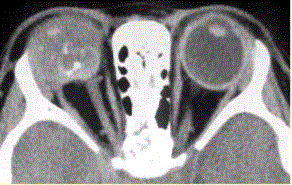

问题 患儿男,1岁,发现左眼白瞳2个月,头部CT显示如下图。 诊断应为

选项 A.成视网膜细胞瘤 B.脉络膜血管瘤 C.海绵状血管瘤 D.脉络膜黑色素瘤 E.脉络膜骨瘤

答案 A